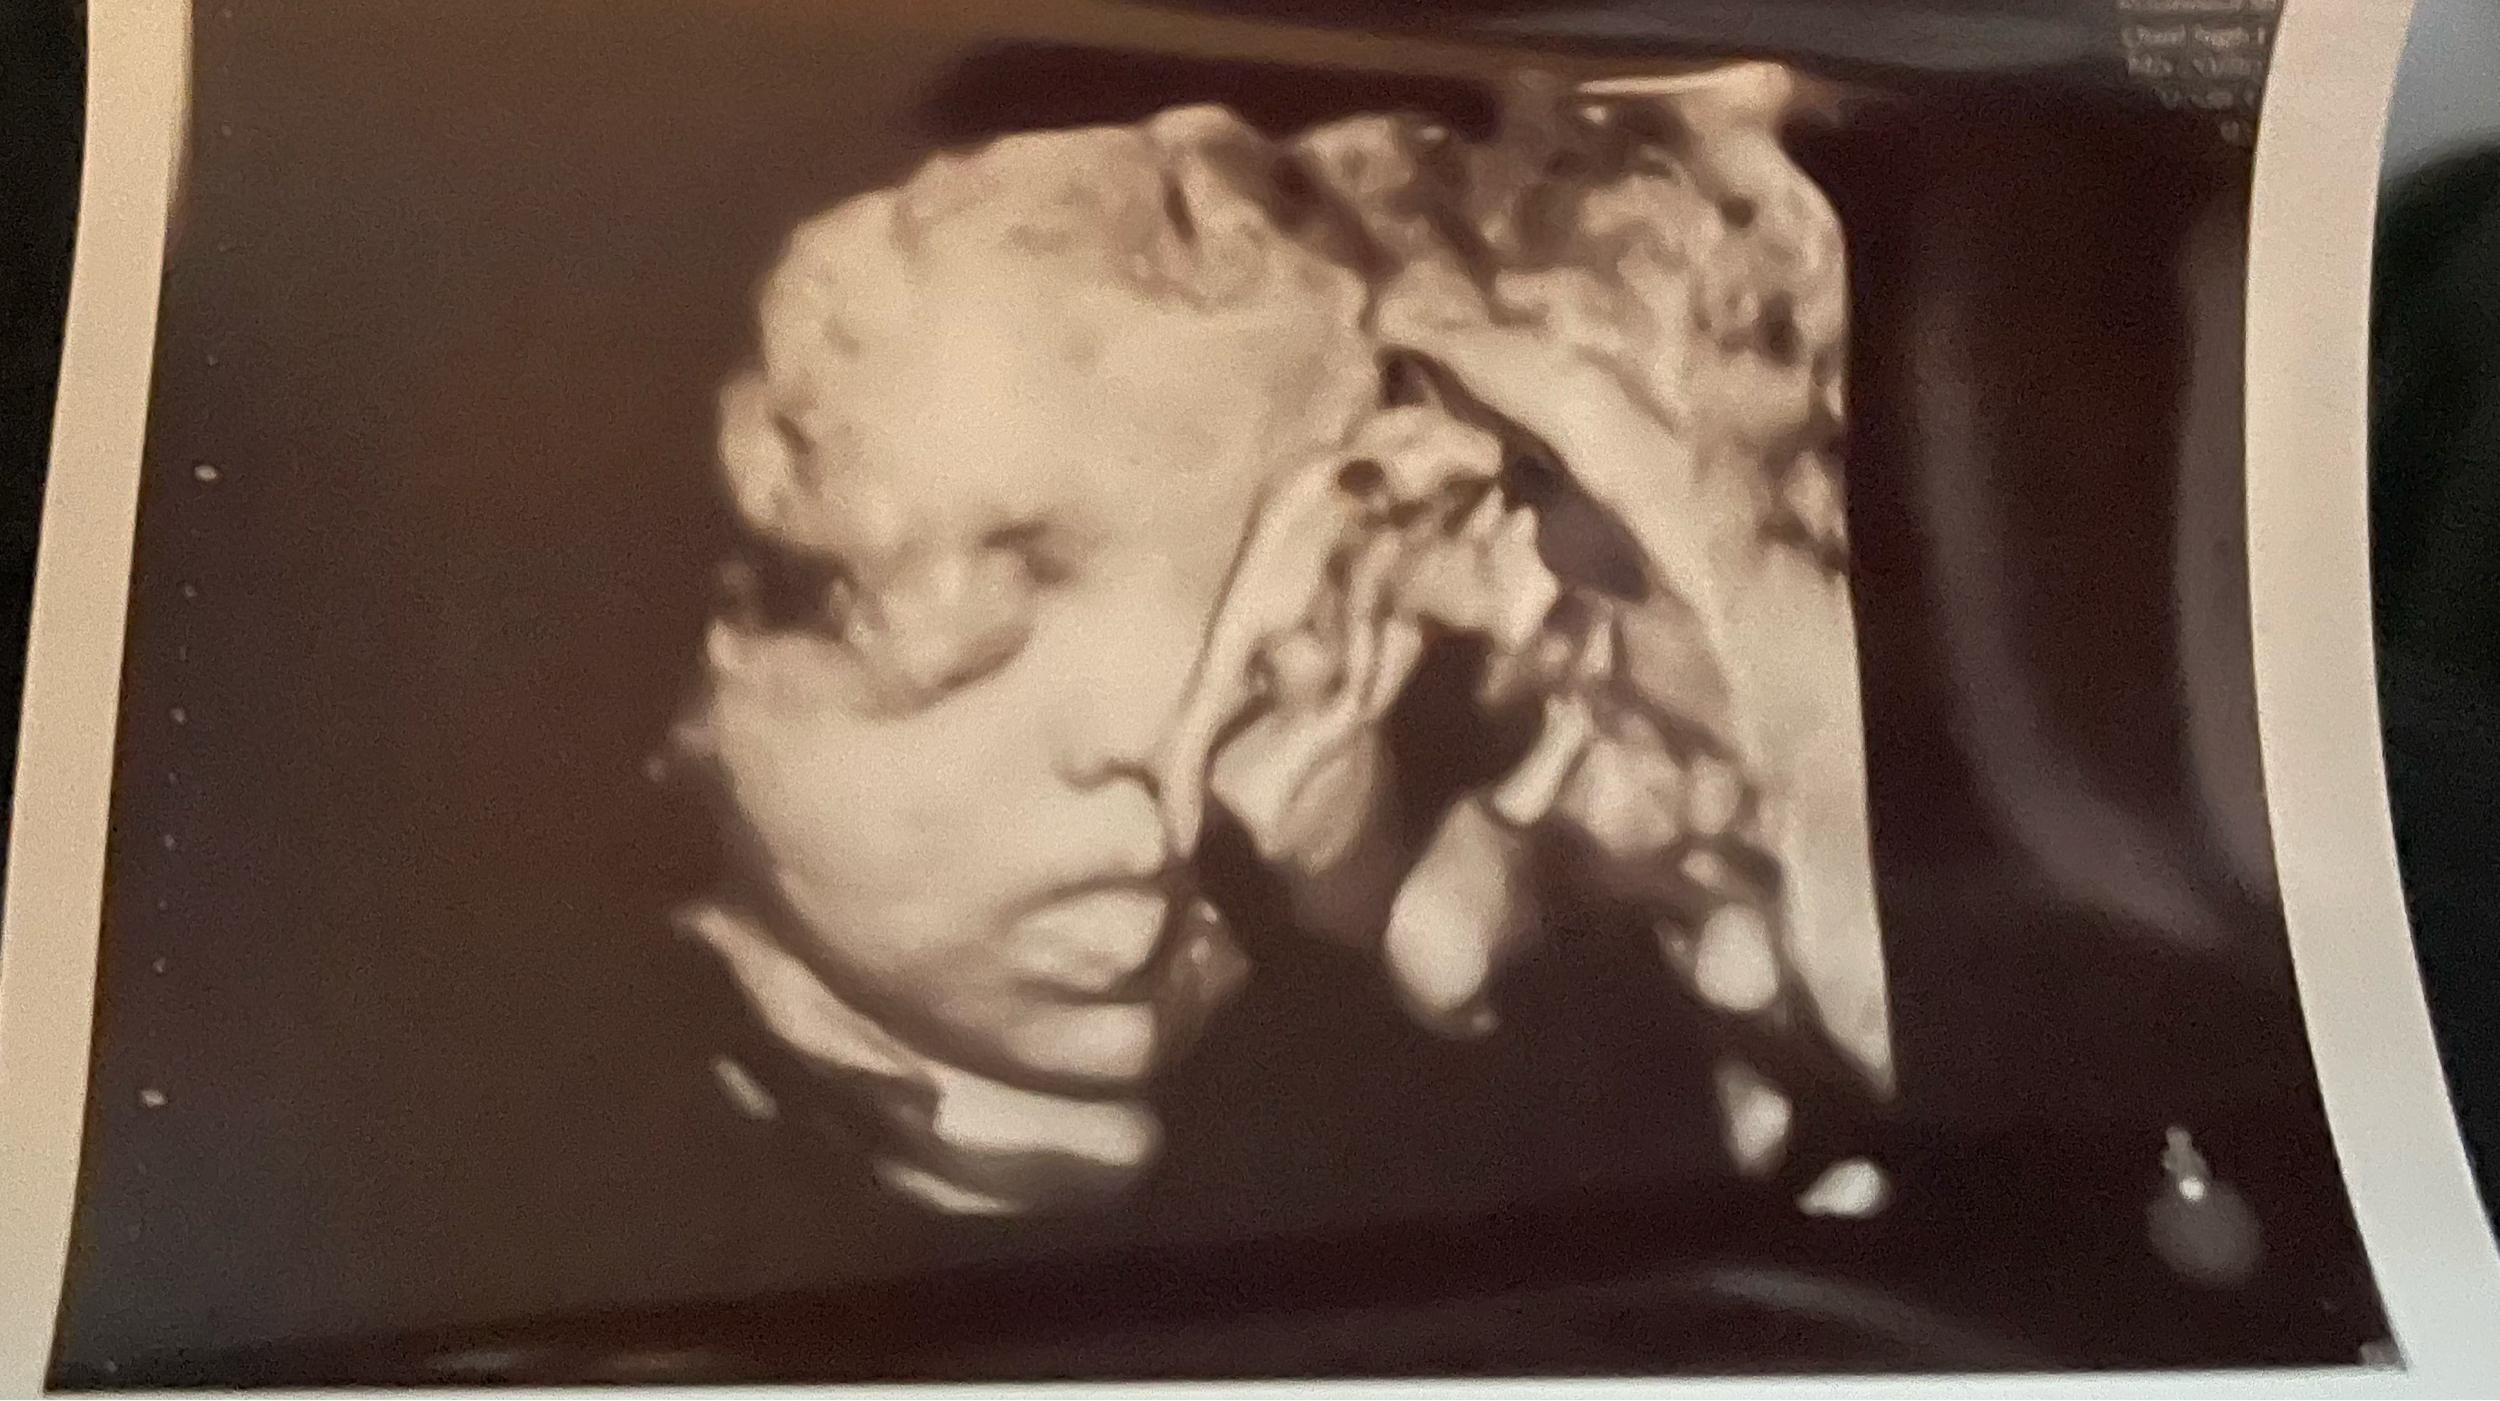

Katie and Mason's Baby Registry

Arrival date April 20, 2024

Hello! Thank you Family and Friends for looking to aid us in this unexpected but happy adventure we’re about to embark on. It truly does take a village and we are grateful to have your support